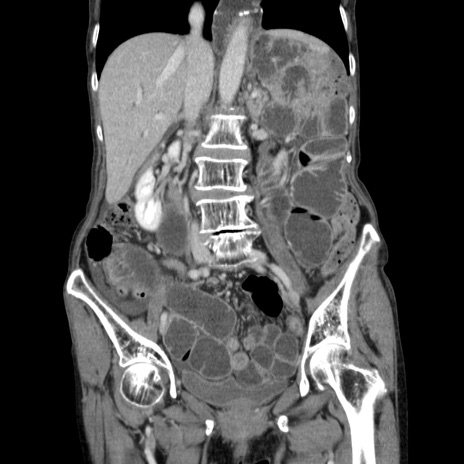

症例25(冠状断像)

【症例】80歳代女性

【主訴】胸のつかえ感

【現病歴】約9時間前に食後から胸のつかえた感じあり、嘔吐あり、来院。

【既往歴】胃癌(全摘)、胆摘、虫垂炎

【身体所見】心窩部に圧痛あり、反跳痛なし。

【データ】WBC 5700、CRP 0.05

横断像